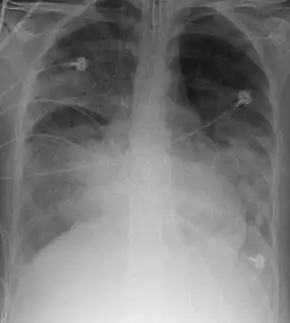

X-ray

Chest X-ray is the most common method used for diagnosis,[36] and may be used to confirm a diagnosis already made using clinical signs.[19] Consolidated areas appear white on an X-ray film.[41] Contusion is not typically restricted by the anatomical boundaries of the lobes or segments of the lung.[26][42][43] The X-ray appearance of pulmonary contusion is similar to that of aspiration,[31] and the presence of hemothorax or pneumothorax may obscure the contusion on a radiograph.[24] Signs of contusion that progress after 48 hours post-injury are likely to be actually due to aspiration, pneumonia, or ARDS.[8]

Although chest radiography is an important part of the diagnosis, it is often not sensitive enough to detect the condition early after the injury.[34] In a third of cases, pulmonary contusion is not visible on the first chest radiograph performed.[5] It takes an average of six hours for the characteristic white regions to show up on a chest X-ray, and the contusion may not become apparent for 48 hours.[5][26][42] When a pulmonary contusion is apparent in an X-ray, it suggests that the trauma to the chest was severe and that a CT scan might reveal other injuries that were missed with X-ray.[44]